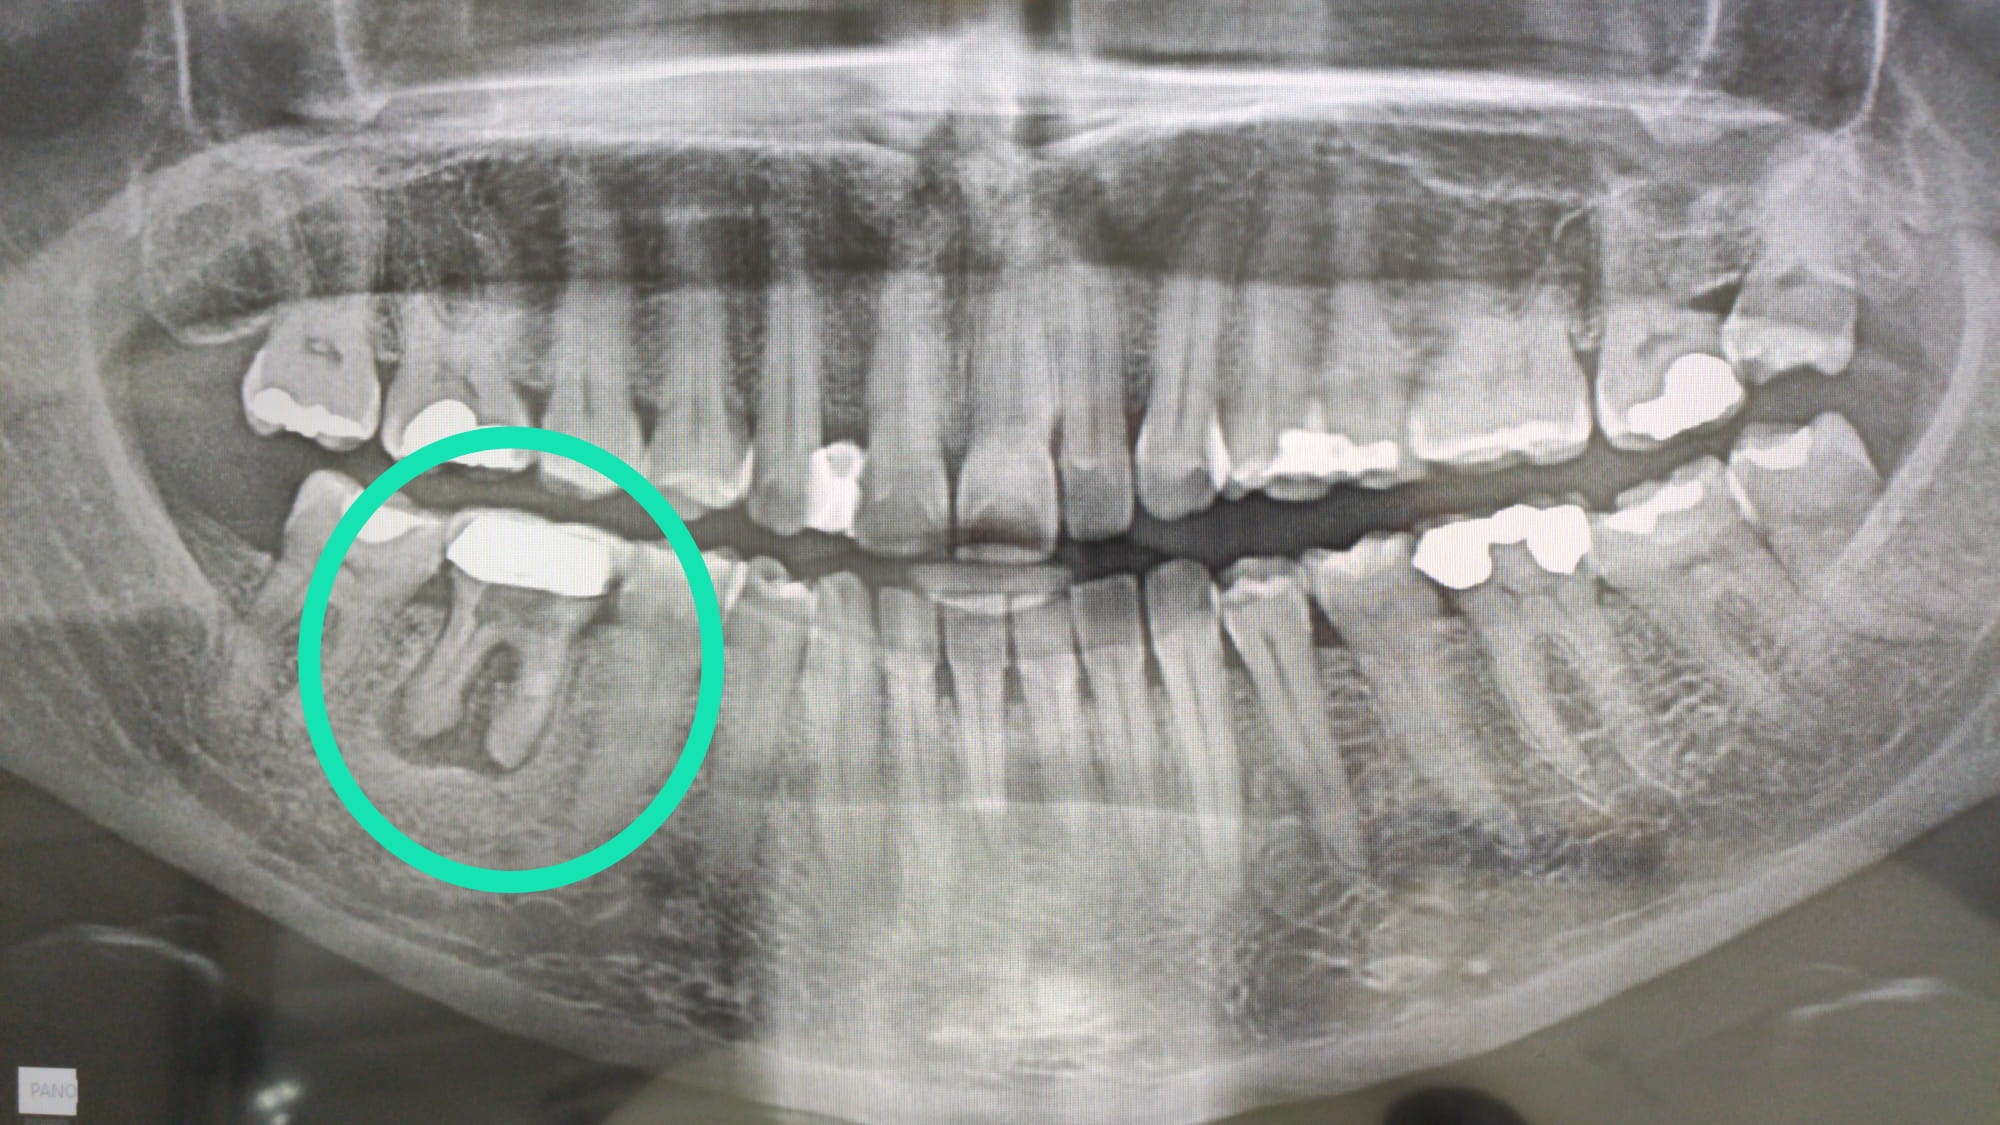

Absceso Dental Que Tomar. también conocido como flemón dental, el absceso debe tratarse cuanto antes y no solo por la aflicción que supone, sino por el daño que causa en las estructuras internas del diente. Además de examinar el diente y el área alrededor de este, el dentista puede hacer lo siguiente:. un absceso dental es una acumulación de pus causada por una infección bacteriana. los síntomas de un absceso dental son dolor severo en la boca y la mandíbula, hinchazón de la encía o la cara y posiblemente,. En el consultorio del dentista, el tratamiento para un absceso gingival. las opciones de tratamiento para un absceso gingival incluyen: en dentaly te hemos preparado el artículo más completo de la red sobre este tipo de afección dental para que conozcas en detalle qué es un absceso. En este artículo, te explicamos de manera sencilla los signos de que tienes un absceso, el tratamiento indicado para curarlo y formas de aliviar el. si experimenta dolor de un absceso dental antes de poder ver a un dentista, hay algunas medidas que puede tomar para aliviar el.

si experimenta dolor de un absceso dental antes de poder ver a un dentista, hay algunas medidas que puede tomar para aliviar el. también conocido como flemón dental, el absceso debe tratarse cuanto antes y no solo por la aflicción que supone, sino por el daño que causa en las estructuras internas del diente. En el consultorio del dentista, el tratamiento para un absceso gingival. las opciones de tratamiento para un absceso gingival incluyen: un absceso dental es una acumulación de pus causada por una infección bacteriana. en dentaly te hemos preparado el artículo más completo de la red sobre este tipo de afección dental para que conozcas en detalle qué es un absceso. los síntomas de un absceso dental son dolor severo en la boca y la mandíbula, hinchazón de la encía o la cara y posiblemente,. En este artículo, te explicamos de manera sencilla los signos de que tienes un absceso, el tratamiento indicado para curarlo y formas de aliviar el. Además de examinar el diente y el área alrededor de este, el dentista puede hacer lo siguiente:.

Absceso Dental Que Tomar En este artículo, te explicamos de manera sencilla los signos de que tienes un absceso, el tratamiento indicado para curarlo y formas de aliviar el. En este artículo, te explicamos de manera sencilla los signos de que tienes un absceso, el tratamiento indicado para curarlo y formas de aliviar el. las opciones de tratamiento para un absceso gingival incluyen: en dentaly te hemos preparado el artículo más completo de la red sobre este tipo de afección dental para que conozcas en detalle qué es un absceso. En el consultorio del dentista, el tratamiento para un absceso gingival. los síntomas de un absceso dental son dolor severo en la boca y la mandíbula, hinchazón de la encía o la cara y posiblemente,. un absceso dental es una acumulación de pus causada por una infección bacteriana. Además de examinar el diente y el área alrededor de este, el dentista puede hacer lo siguiente:. también conocido como flemón dental, el absceso debe tratarse cuanto antes y no solo por la aflicción que supone, sino por el daño que causa en las estructuras internas del diente. si experimenta dolor de un absceso dental antes de poder ver a un dentista, hay algunas medidas que puede tomar para aliviar el.